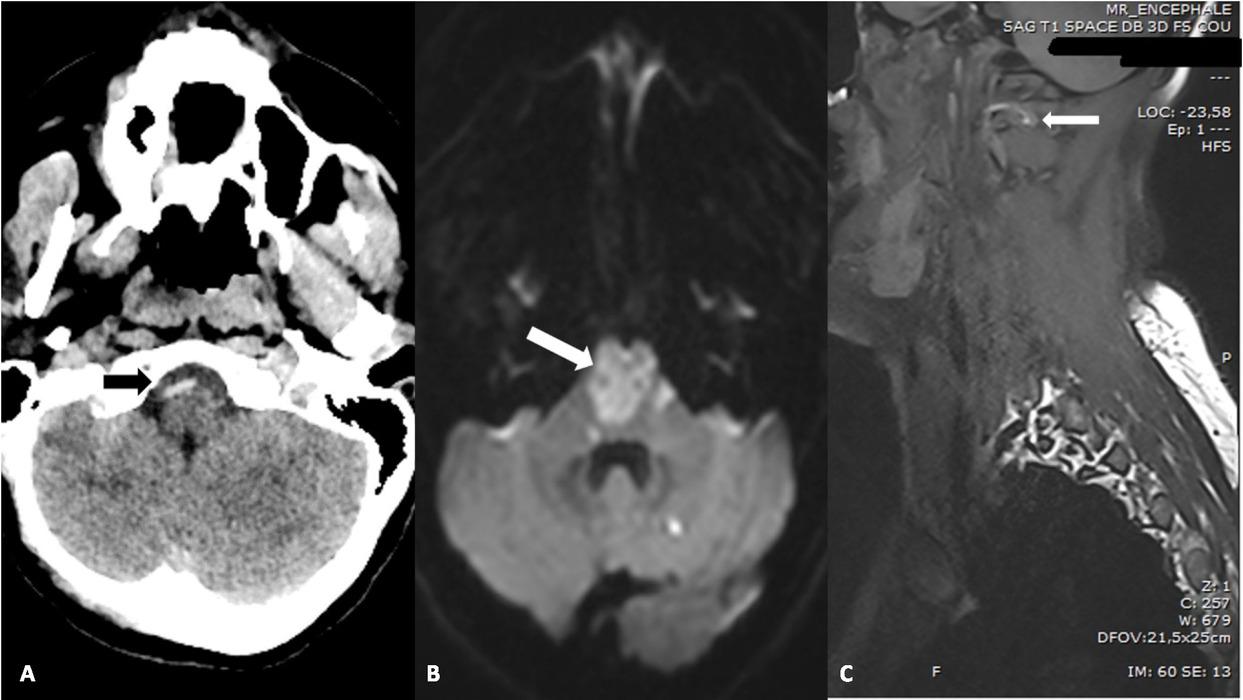

Fig. 1